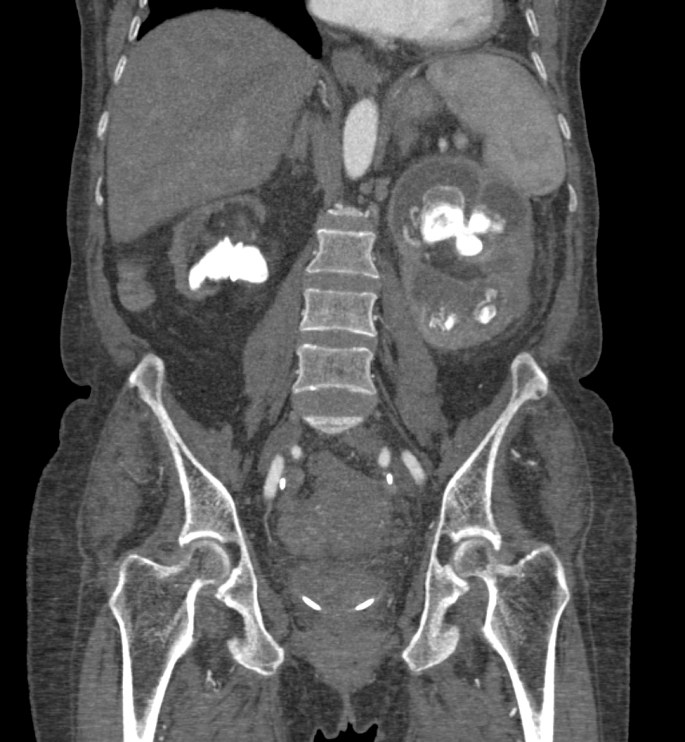

Tomografía Computarizada:

Es la técnica de elección por dos razones:

- Alta especificidad y definición de los hallazgos que permiten confirmar el diagnóstico.

- Descartar afectación extrerrenal y Planificación quirúrgica.

Estos hallazgos son altamente sujestivos de PNXG:

- Aumento difuso del tamaño y pérdida del contorno renal.

- Litiasis coraliforme: cálculo central en pelvis renal contraída (también puede existir calcificaciones intraparenquimatosas). La TC es la mejor técnica para identificar las litiasis.

- Riñón no funcionante (pobre o nula eliminación del medio de contraste en el riñón afectado).

- Cálices renales dilatados (áreas hipodensas) de apariencia multiloculada que se asemeja a una «pata de oso».

- También pueden darse abscesos o áreas de necrosis parenquimatosa.

- Cambios inflamatorios que excede los límites del riñón y genera colecciones periféricas o extensión hacia vísceras vecinas. Pueden darse abscesos en el psoas y fístulas (cutáneas o colónicas) que indican progresión de la enfermedad.

Aunque el área de hipoatenuación que se extiende desde la pelvis renal contraída hasta los cálices renales puede sugerir una hidronefrosis, la baja atenuación corresponde más bien a tejido inflamatorio antes que a líquido (la nefrostomía percutánea no siempre se lleva a cabo).

Veamos un caso.

Paciente mujer de 62 años que acude por decaimiento general con fiebre y dolor en flanco izquierdo. Ingresa en UVI por signos de sepsis

Nos cuenta antecedentes de pielonefritis e hidronefrosis crónica.

Hallazgos en imagen:

Estos hallazgos pueden ser dificiles de interpretar, ya que una paciente con hidronefrosis crónica y litiasis en el uréter puede haber sufrido una obstrucción que origina un cuadro de dolor en FRI con ruptura de cálices y colección extra axial. Otra probabilidad puede ser un angiomiolipoma que ha roto un aneurisma y ha producido un sangrado. También podríamos estar ante una pionefrosis aunque dada dada la clínica, los antecedentes y al observar los hallazgos en TC podríamos establecer la sospecha de pielonefritis xantunogranulomatosa con alta probabilidad. La confrimación vendrá dada con la nefrostomía y estudio de anatomía patológica.